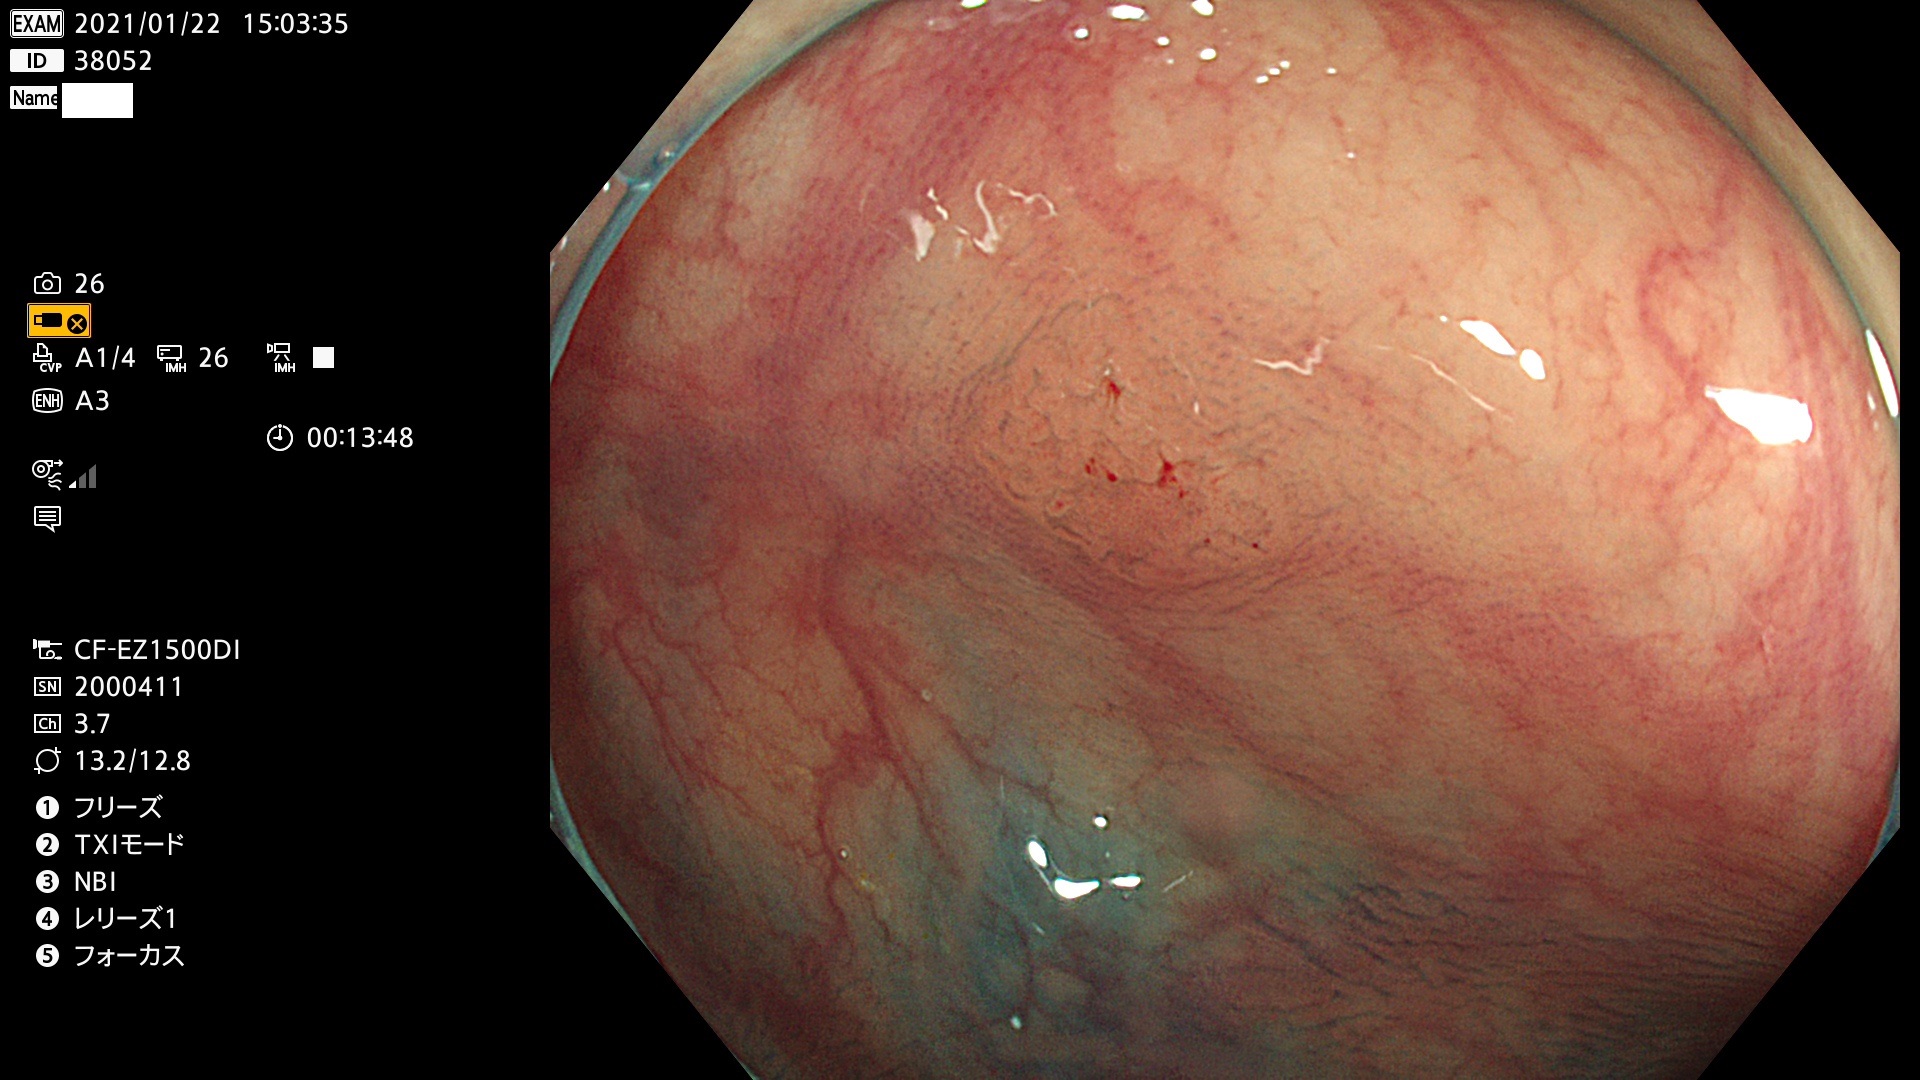

38001 38002 38003 38004 38006(SSAPのみ) 38007 38008 38009 38010 38012 38013 38014 38016 38018 38020 38021 38025 38026 38029 38032 38033 38034 38035 38036 38037(SSAPのみ) 38039 38043 38044 38048 38049 38050 38052 38055 38056 38057 38058 38059 38064(SSAPのみ) 38065 38068 38069 38070 38071 38072 38074 38075 38076 38078 38079 38080 38082 38083 38084 38085(SSAPのみ) 38086 38087 38088 38089 38090 38091 38092 38093 38094 38097 38098 38099

発見困難で危険性の高い平坦型病変(上記100名より抽出)